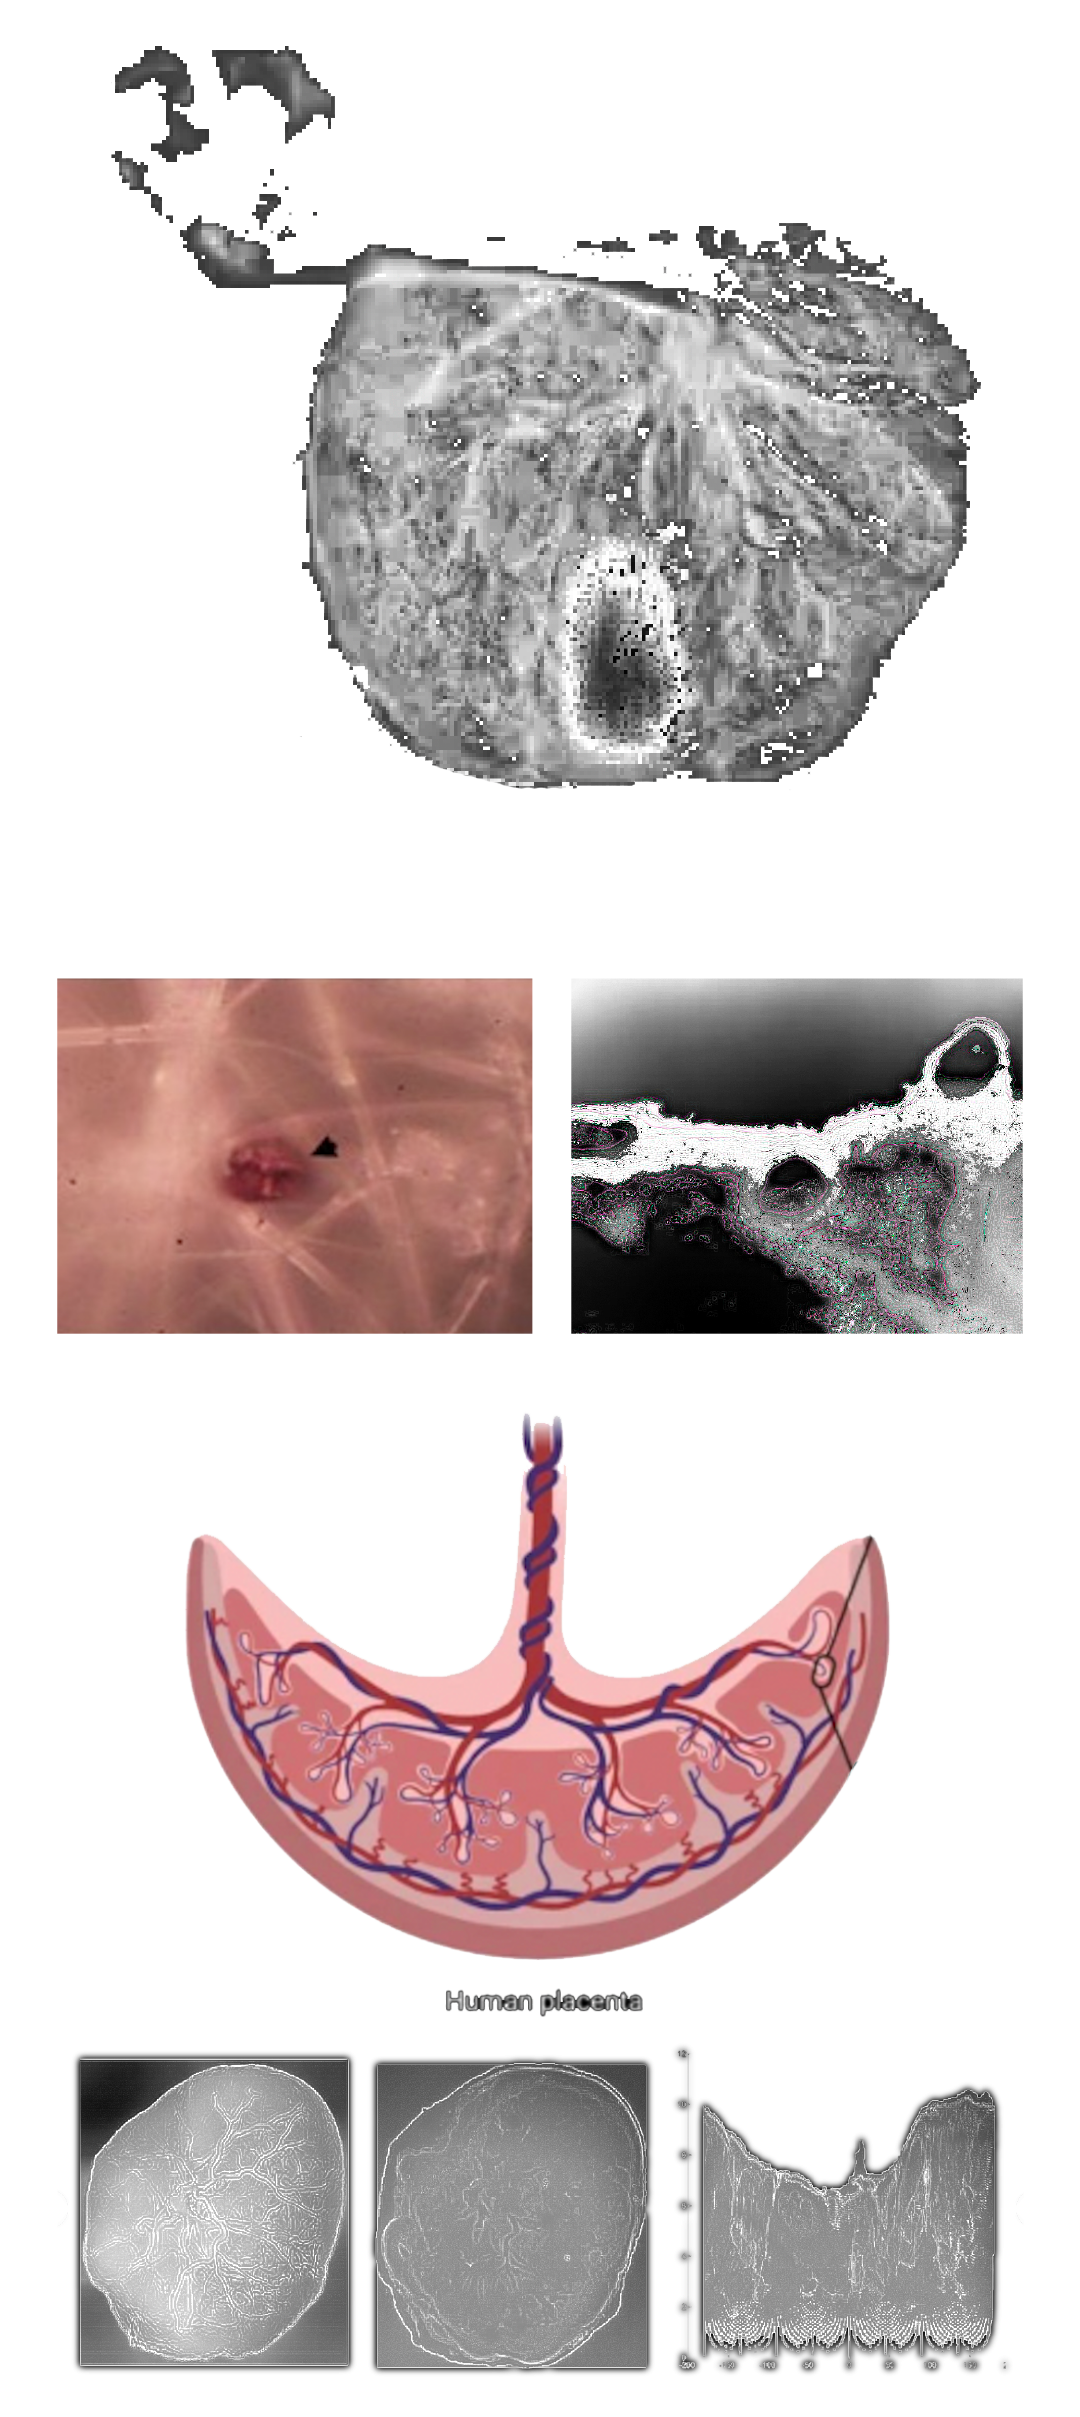

MICROPLASTICS (MPS) ARE DEFINED AS PLASTIC PARTICLES SMALLER THAN 5 MM. THEY HAVE BEEN FOUND ALMOST EVERYWHERE THEY HAVE BEEN SEARCHED FOR AND RECENT DISCOVERIES HAVE ALSO DEMONSTRATED THEIR PRESENCE IN HUMAN PLACENTA, BLOOD, MECONIUM, AND BREASTMILK, BUT THEIR LOCATION AND TOXICITY TO HUMANS HAVE NOT BEEN REPORTED TO DATE. THE AIM OF THIS STUDY WAS TWOFOLD:

1. TO LOCATE MPS WITHIN THE INTRA/EXTRACELLULAR COMPARTMENT IN HUMAN PLACENTA.

2. TO UNDERSTAND WHETHER THEIR PRESENCE AND LOCATION ARE ASSOCIATED WITH POSSIBLE STRUCTURAL CHANGES OF CELL ORGANELLES. USING VARIABLE PRESSURE SCANNING ELECTRON MICROSCOPY AND TRANSMISSION ELECTRON MICROSCOPY, MPS HAVE BEEN LOCALIZED IN TEN HUMAN PLACENTAS. IN THIS STUDY, WE DEMONSTRATED FOR THE FIRST TIME THE PRESENCE AND LOCALIZATION IN THE CELLULAR COMPARTMENT OF FRAGMENTS COMPATIBLE WITH MPS IN THE HUMAN PLACENTA AND WE HYPOTHESIZED A POSSIBLE CORRELATION BETWEEN THEIR PRESENCE AND IMPORTANT ULTRASTRUCTURAL ALTERATIONS OF SOME INTRACYTOPLASMIC ORGANELLES (MITOCHONDRIA AND ENDOPLASMIC RETICULUM). THESE ALTERATIONS HAVE NEVER BEEN REPORTED IN NORMAL HEALTHY TERM PREGNANCIES UNTIL TODAY. THEY COULD BE THE RESULT OF A PROLONGED ATTEMPT TO REMOVE AND DESTROY THE PLASTIC PARTICLES INSIDE THE PLACENTAL TISSUE. THE PRESENCE OF VIRTUALLY INDESTRUCTIBLE PARTICLES IN TERM HUMAN PLACENTA COULD CONTRIBUTE TO THE ACTIVATION OF PATHOLOGICAL TRAITS, SUCH AS OXIDATIVE STRESS, APOPTOSIS, AND INFLAMMATION, CHARACTERISTIC OF METABOLIC DISORDERS UNDERLYING OBESITY, DIABETES, AND METABOLIC SYNDROME AND PARTIALLY ACCOUNTING FOR THE RECENT EPIDEMIC OF NON-COMMUNICABLE DISEASES.

1. TO LOCATE MPS WITHIN THE INTRA/EXTRACELLULAR COMPARTMENT IN HUMAN PLACENTA.

2. TO UNDERSTAND WHETHER THEIR PRESENCE AND LOCATION ARE ASSOCIATED WITH POSSIBLE STRUCTURAL CHANGES OF CELL ORGANELLES. USING VARIABLE PRESSURE SCANNING ELECTRON MICROSCOPY AND TRANSMISSION ELECTRON MICROSCOPY, MPS HAVE BEEN LOCALIZED IN TEN HUMAN PLACENTAS. IN THIS STUDY, WE DEMONSTRATED FOR THE FIRST TIME THE PRESENCE AND LOCALIZATION IN THE CELLULAR COMPARTMENT OF FRAGMENTS COMPATIBLE WITH MPS IN THE HUMAN PLACENTA AND WE HYPOTHESIZED A POSSIBLE CORRELATION BETWEEN THEIR PRESENCE AND IMPORTANT ULTRASTRUCTURAL ALTERATIONS OF SOME INTRACYTOPLASMIC ORGANELLES (MITOCHONDRIA AND ENDOPLASMIC RETICULUM). THESE ALTERATIONS HAVE NEVER BEEN REPORTED IN NORMAL HEALTHY TERM PREGNANCIES UNTIL TODAY. THEY COULD BE THE RESULT OF A PROLONGED ATTEMPT TO REMOVE AND DESTROY THE PLASTIC PARTICLES INSIDE THE PLACENTAL TISSUE. THE PRESENCE OF VIRTUALLY INDESTRUCTIBLE PARTICLES IN TERM HUMAN PLACENTA COULD CONTRIBUTE TO THE ACTIVATION OF PATHOLOGICAL TRAITS, SUCH AS OXIDATIVE STRESS, APOPTOSIS, AND INFLAMMATION, CHARACTERISTIC OF METABOLIC DISORDERS UNDERLYING OBESITY, DIABETES, AND METABOLIC SYNDROME AND PARTIALLY ACCOUNTING FOR THE RECENT EPIDEMIC OF NON-COMMUNICABLE DISEASES.